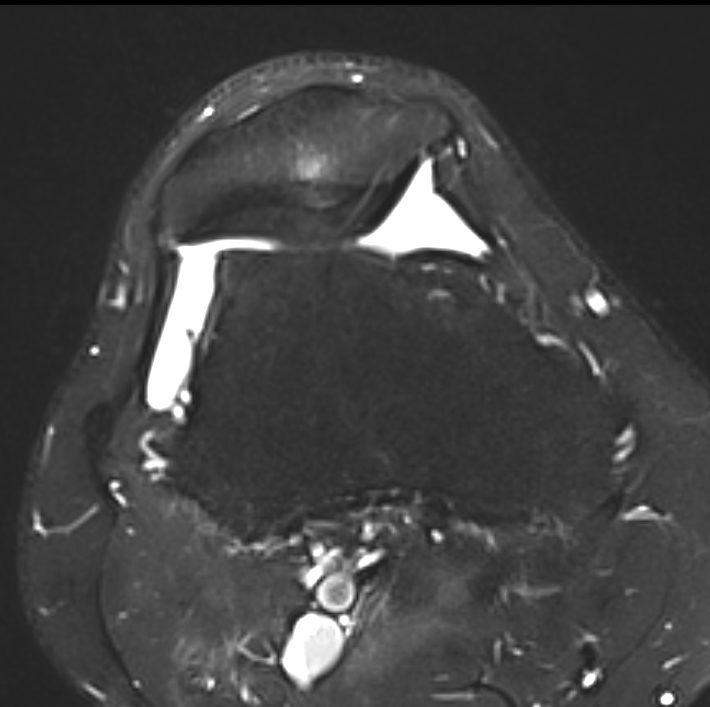

3. MPFL reconstruction (with TTT, or if TTTG < 20)

- acts as checkrein to lateral displacement

- usually harvest hamstring autograft

- medial incision

- beware overtightening (will give pain) / patella fracture (drill holes in patella)

- reassess for stability